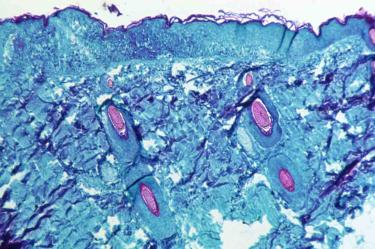

El brote mundial de viruela del mono ya es emergencia de salud, de acuerdo con la declaración de la OMS este sábado 23 de julio.

En México hace algunas semanas se confirmó el primer caso de viruela símica en México y de inmediato el tema se volvió tendencia en las redes sociales preguntando recomendaciones contra la viruela del mono.

De acuerdo con los expertos de Salud, esta enfermedad se transmite principalmente de animales infectados a humanos y el periodo de incubación puede ser de hasta trece días tras el contacto.